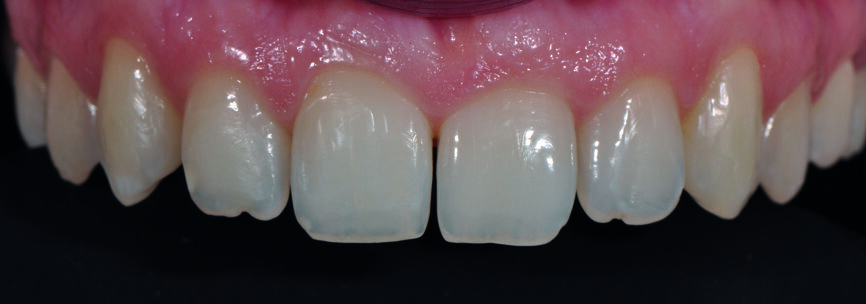

Fig. 6 : a) Gros plan du sourire après la fermeture du diastème avec le composite Essentia (GC).

Fig 6 c) : vue intraorale de face. La teinte du composite est bien intégrée, quelle que soit la direction d’où l’on regarde, indépendamment de la lumière incidente